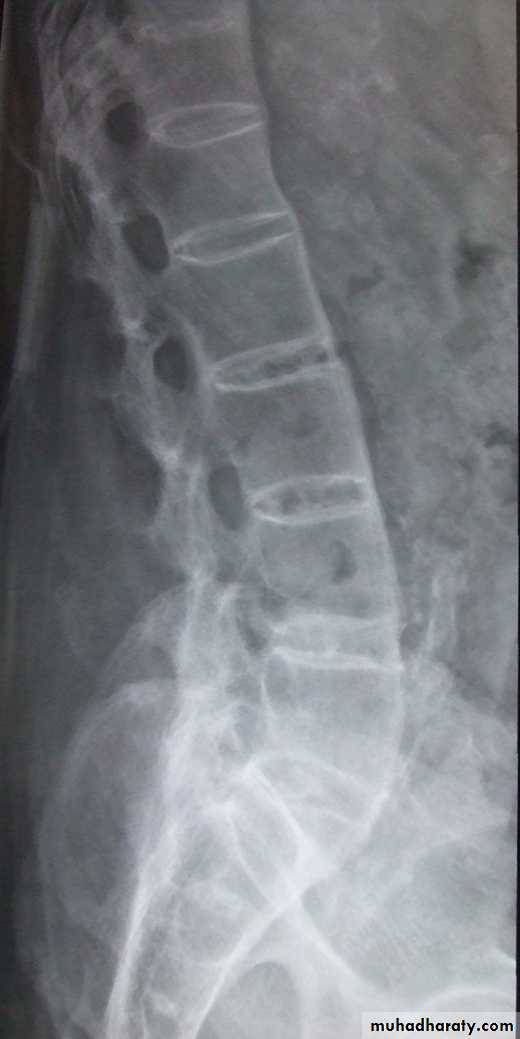

Lumbar spondylosis. There is distal narrowing and a vacuum

phenomenon is present in the degenerative discs. Marginal osteophytes arepresent. Inferiorly the facet joints show features of degeneration and, with the increase in lordosis, the spinous processes are in contact